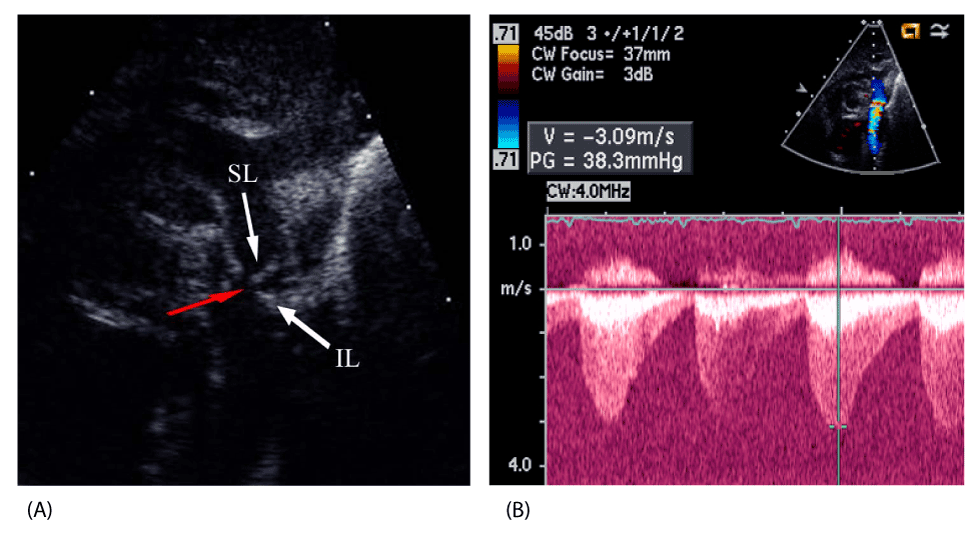

| Figure 1: A. 2D TTE demonstrating the coarctation ledge (white arrows) encompassing and narrowing the origin of the LSA (red arrow). B. Spectral Doppler interrogation demonstrating the double velocity envelope with antegrade flow in diastole consistent with coarctation of the aorta. The peak gradient across the coarctation is 38 mmHg. Key: 2D TTE – two dimensional transthoracic echocardiogram, IL – inferior aspect of the coarctation ledge, LSA – left subclavian artery, SL – superior aspect of the coarctation ledge. |